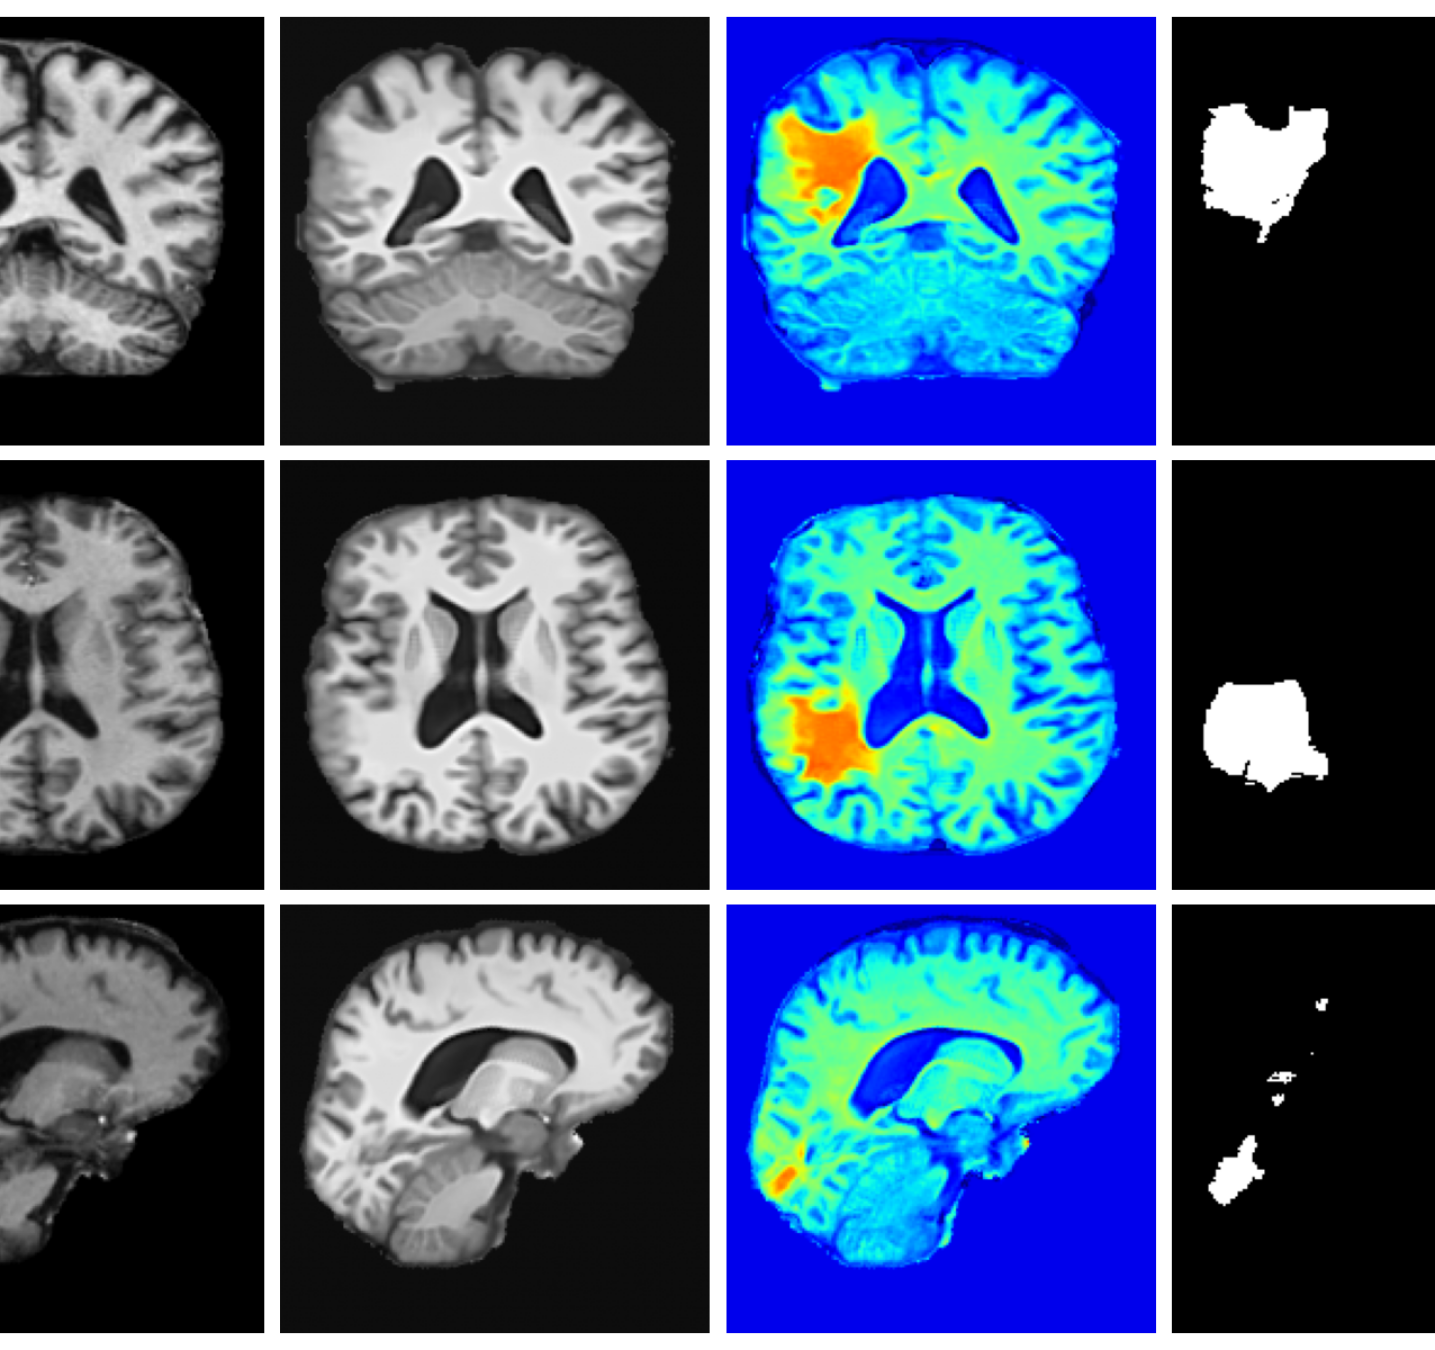

Qualitative T1w results are shown in Figure 2, with further examples for other modalities in Appendix A.8. LoHiResGAN and Res-SRDiff produce unrealistic images with severe artifacts, likely arising from bias fields, sharp intensity artifacts, and other noise not present during training. UniRes generates oversmoothed images, likely due to its TV prior and its reliance on information from multiple input modalities, whereas we apply it unimodally. Di-Fusion shows less pronounced but still notably blurry, voxelated reconstructions which lack the fine-grained details generate by our method. This is likely, in part, due to our use of synthetic rather than real noisy training data, which the method was designed for. As such data is scarce, and in our case unavailable, this requirement represents a significant limitation of Di-Fusion. SynthSR, whilst not as well as our method, does preserve key anatomical structures. However, our difference maps show reduced contrast, further supporting the strong quantitative results shown in Table 2.

Figure 3 (additional examples in Appendix A.9) shows that SynthSR preserves healthy tissue but struggles with large lesions, while DDPM-2D and DDPM-3D, despite producing high-contrast anomaly maps, generate unrealistic homogeneous inpainting, consistent with their lower performance in Table 3. In contrast, our method yields the most anatomically plausible inpainted regions, although anomaly maps appear subtle due to low contrast between lesions and healthy tissue.

A.8 Additional qualitative restoration results

Additional qualitative results for the Clinical dataset are given in Figures 7, 8 and 9, and for the Low-field dataset in Figures 10 and 11.

A.9 Additional qualitative inpainting results

Additional qualitative results for the ATLAS and BraTS datasets are given in Figures 12 and 13, respectively.